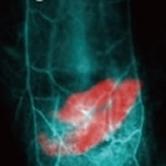

NIR-II活体成像技术能够提供更深层次的组织成像,对于研究生物体内的生理和病理过程具有重要意义。活体成像仪可以实时、动态地观察动物体内的生物活动,为药物研发、疾病模型研究等提供了有力的工具。动物活体光学设备则可以利用光学原理,对动物进行高分辨率的成像,帮助科研人员更清晰地了解生物体内的结构和功能。X射线活体设备能够提供动物体内骨骼、器官等的详细影像,对于研究骨骼发育、疾病诊断等方面有着重要的作用。全光谱动物活体设备则可以在多个光谱范围内进行成像,提供更全面的生物信息。